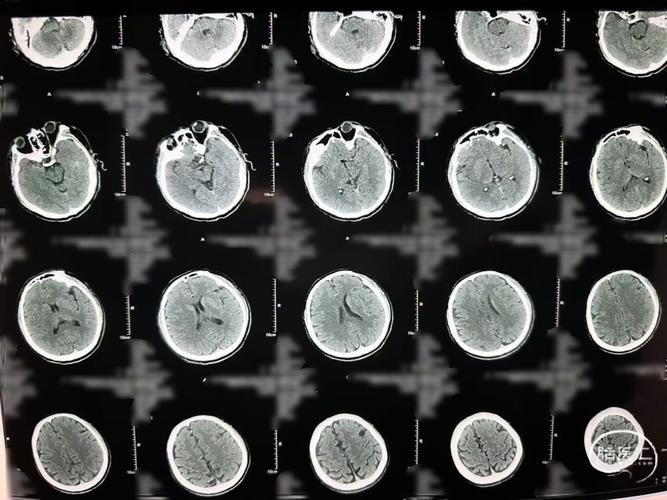

最典型的直接征象:低密度灶

- 表现:在脑的某个区域,出现一个边界相对清晰或不清晰的、密度比周围正常脑组织要低的区域,在黑白CT片上,这通常显示为灰色或黑色,而正常脑组织是均匀的灰白色。

- 特点:

- 位置:这个低密度灶的位置必须与患者的神经功能缺损症状相匹配,患者左侧肢体无力,那么CT上应该在右侧大脑半球(控制左侧肢体的区域)发现低密度灶。

- 形态:轻度脑梗的低密度灶可能很小,形态不规则,或者呈楔形(尖端指向脑中心,基底朝向脑表面)。

- 边界:早期边界可能模糊,随着时间推移,边界会变得清晰。

- 脑沟变浅、模糊:缺血区域的脑组织因为早期水肿,会导致局部的脑沟(脑表面的沟回)变浅、变平,甚至消失,这通常是CT上最早能观察到的变化之一。

- 脑实质密度轻度减低:整个缺血区域的脑组织密度可能比健侧轻微、均匀地降低一点点,但还没有形成明确的低密度灶,这个变化非常细微,容易忽略。

- 豆状核边缘模糊:这是一个非常经典的早期征象,正常情况下,大脑深部的“豆状核”结构边界非常清晰,当供应它的血管发生缺血时,这个边界会变得模糊不清。